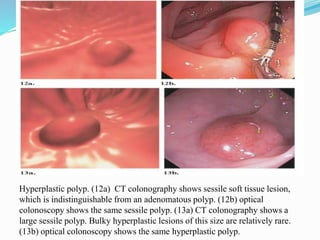

This document discusses colorectal polyps. It defines polyps and describes their types, including neoplastic and non-neoplastic polyps. It discusses adenomatous polyps in depth, noting their malignant potential increases with size over 1cm and villous architecture. Radiological diagnostic methods for polyps including single and double contrast barium enema and CT colonography are explained. The document provides an overview of polyp pathogenesis and genetic syndromes like FAP that increase cancer risk.